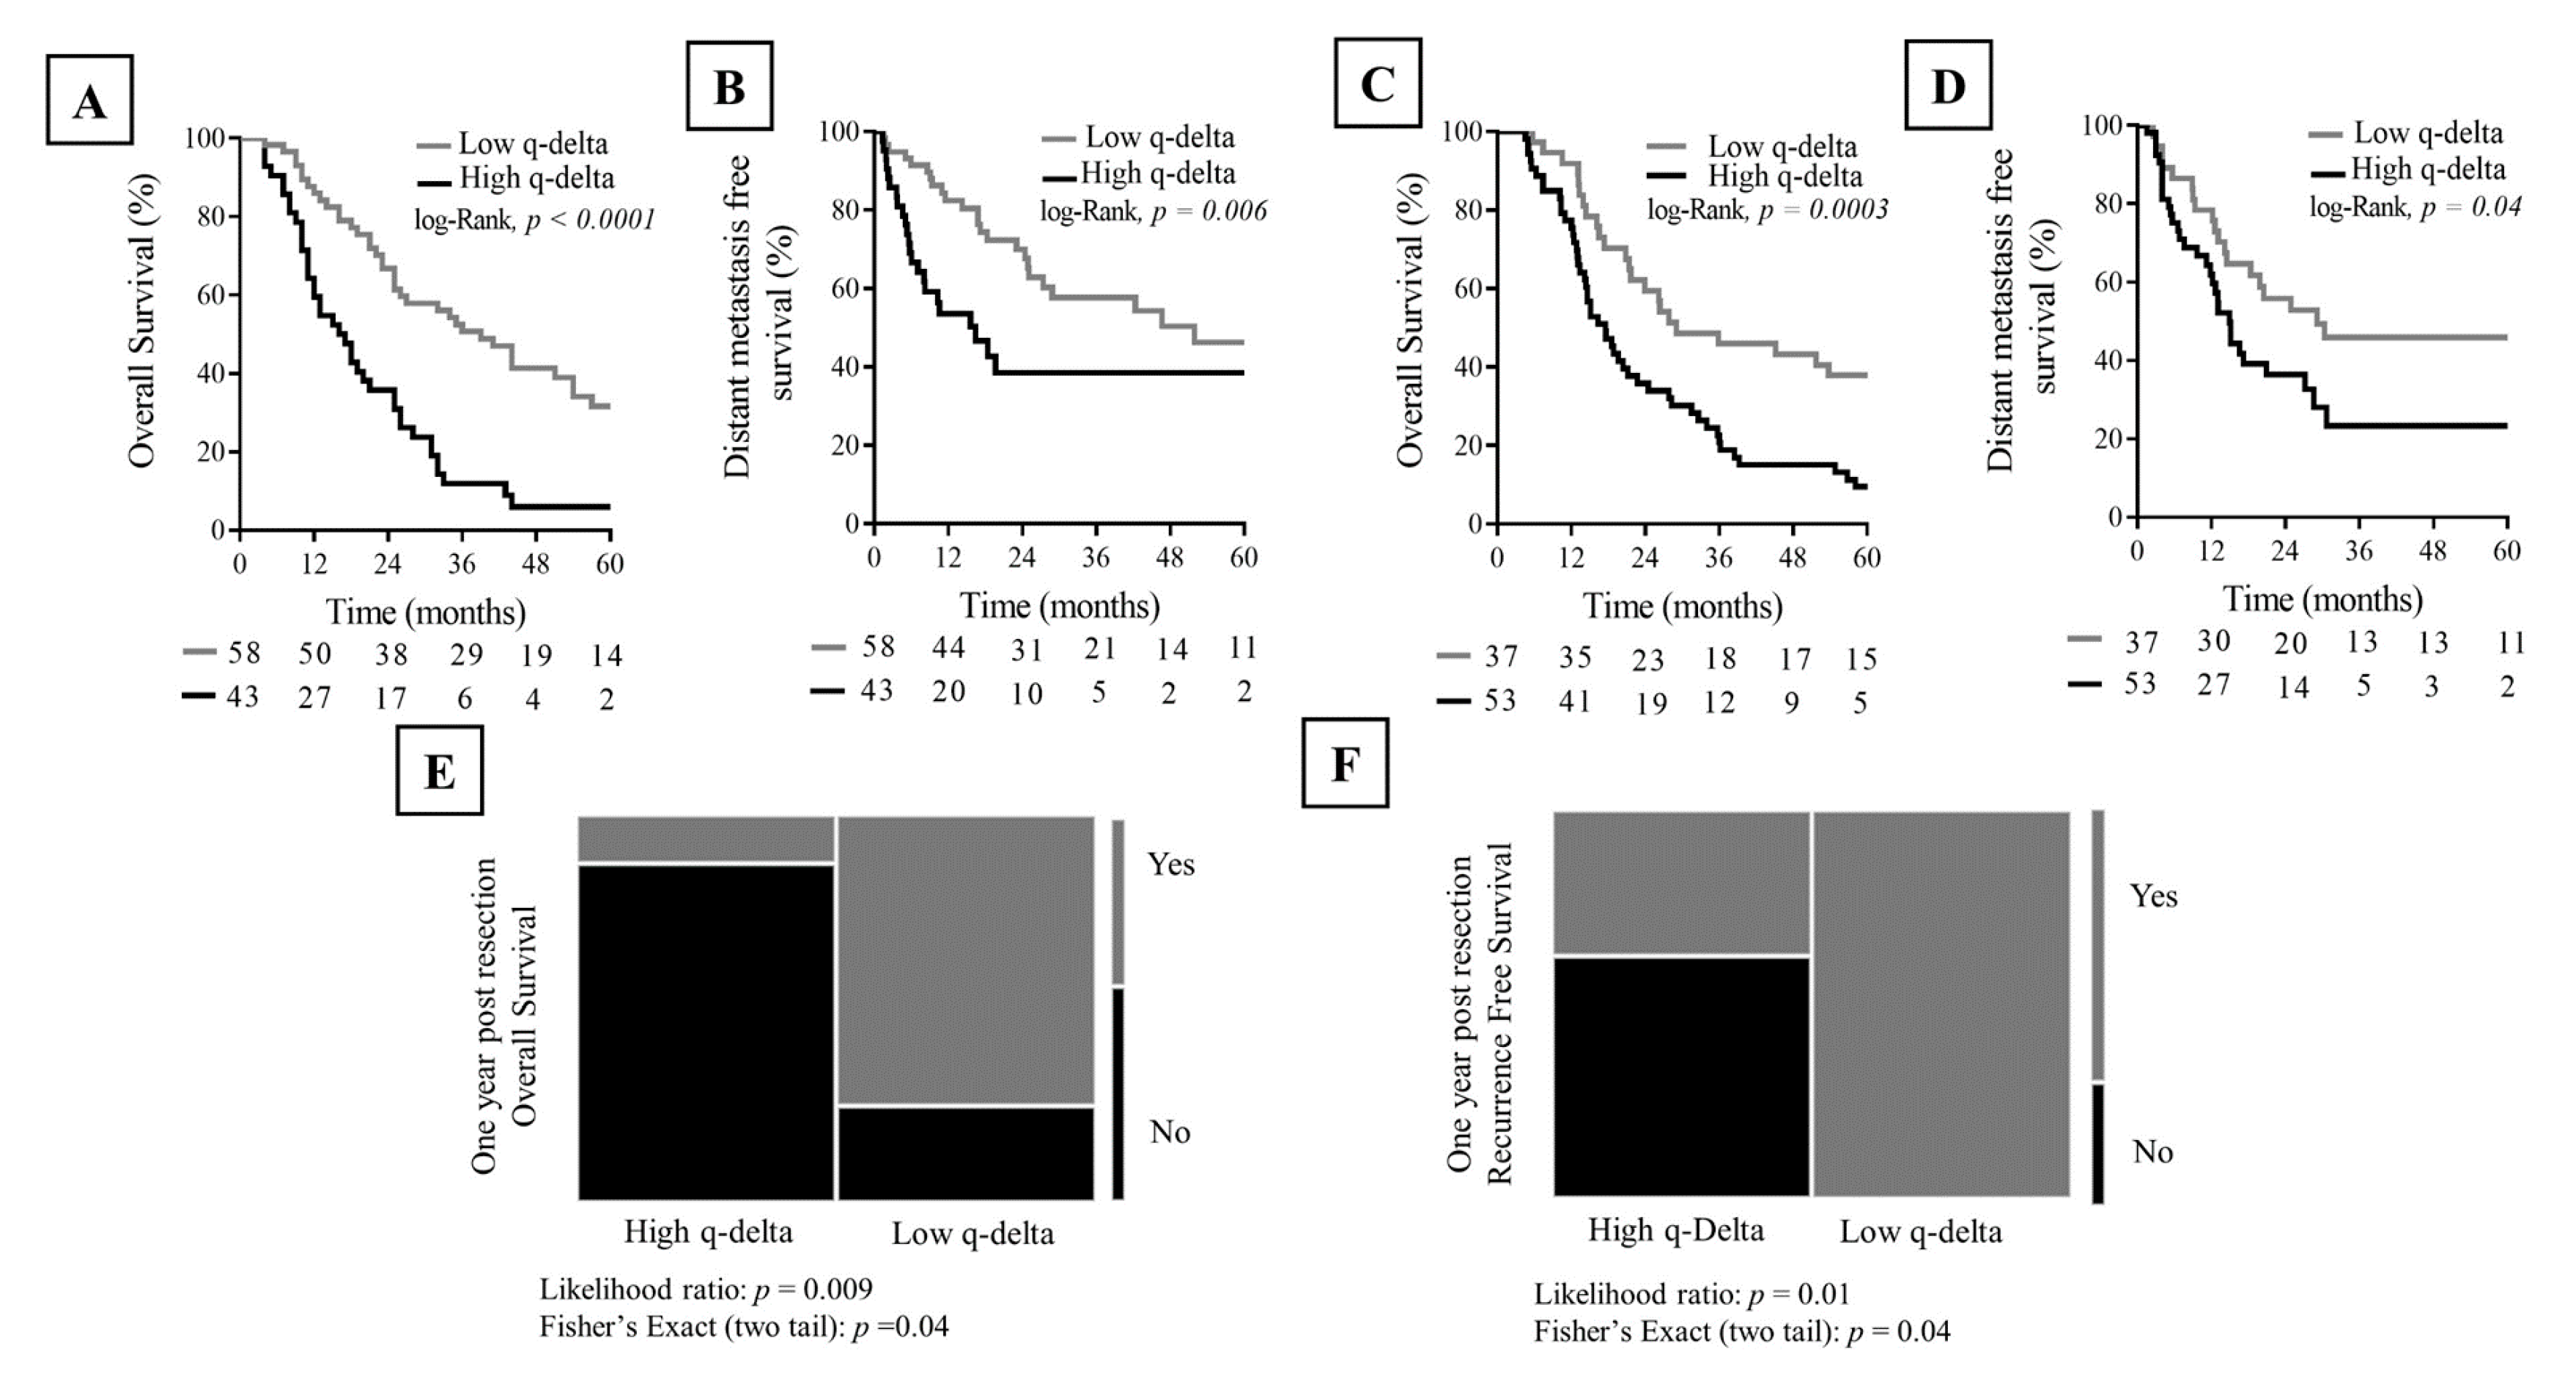

2.6. Association between q-delta and Clinical Outcome

4.8. Statistical Analysis